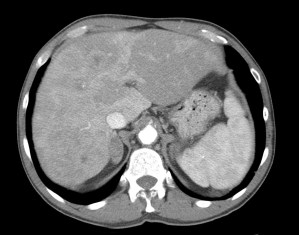

Paciente de 59 años con antecedentes personales de Cá de vejiga.

Se le realiza una Uro-Tc por seguimiento al año, aunque en esta ocasión el paciente refiere episodio de hematuria.

Tras el tratamiento de la recidiva y nefrostomía para la hidroureteronefrosis, vuelve acudir al hospital a los 9 meses por episodio de dolor en FD y malestar general. Se realiza una ecografía de urgencias.

Se realiza nueva TC bifásico abdominopélvio y Uro TC.

- Paciente con numerosas recidivas por Cá vejiga.

- Ha desarrollado un tumor metacrónico en pelvis renal derecha, también responsable de la hidroureteronefrosis.

- Mala evolución radiológica del proceso a expensas de metástasis pulmonares y hepáticas.